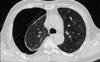

A

Patrón intersticial reticular